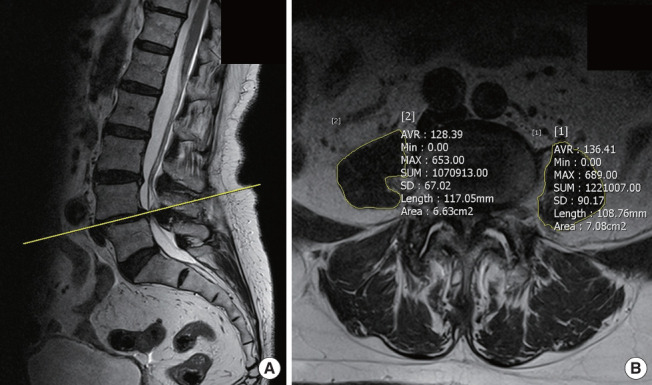

Methods: This retrospective study examined a cohort of 465 patients who underwent OLIF from 2015 to 2023. Patient demographics, comorbidities, pre- and postoperative laboratory test results, and perioperative status were assessed. General condition of patients was assessed using the modified frailty index-11 (mFI-11), prognostic nutrition index, and geriatric nutrition risk index. In OLIF, the size and location of the psoas muscle involved in retraction and its relationship with the vertebral body were also investigated.

Results: POI occurred in 19 patients (4%). Lower mFI-11 was linked to a higher risk of POI. While psoas muscle size had no significant effect on the risk of POI, the anterior location of the psoas muscle relative to the vertebral body was associated with a higher occurrence of POI. Multivariate logistic regression analysis of POI identified mFI-11 as the most significant risk factor (p = 0.003).